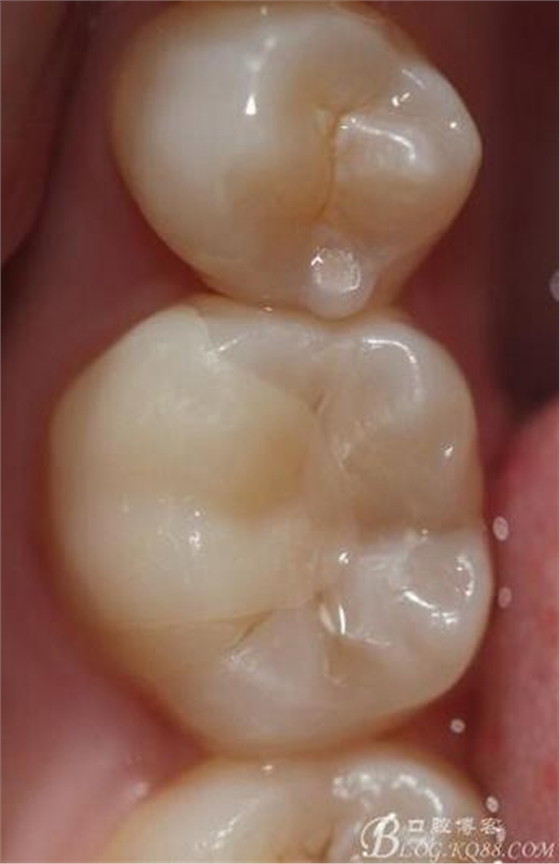

(這個(gè)是這個(gè)是學(xué)后第一次做美學(xué)修復(fù))

第一次做嵌體是樹脂嵌體。做完之后我跟我們主任炫耀,本來是想讓他夸我一下的。沒想到他說:“別高興太早,咱們時(shí)間上看。”說實(shí)話當(dāng)時(shí)心里一點(diǎn)底沒有,到底能用多長時(shí)間,自己一點(diǎn)沒底。